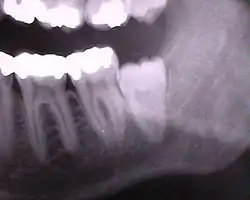

Die folgenden Röntgenbilder sind Ausschnitte aus Orthopantomogrammen (OPG):

Weisheitszähne 48 und 18; Zahn 48 – keine Kippung, Wurzel nur teilweise ausgebildet, Krone teilweise noch knöchern bedeckt